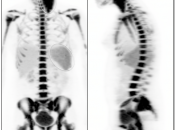

Normal Skeletal Uptake

Mild to moderate FDG uptake can be normally seen within red marrow, most commonly affecting the vertebral bodies, sternum, pelvis, and proximal long bones (it is not unusual to see fairly prominent uptake within the proximal half of the femurs). This red marrow uptake can be quite heterogeneous at times, yet still normal.

Diffuse Skeletal Uptake:

Intense and diffuse reactive marrow uptake is frequently seen as the result of chemotherapy and/or colony stimulating factors (discussed in detail, here).

If rather diffuse and intense uptake is noted without a history of recent chemotherapy or colony stimulating factors, be suspicious of infiltrating disease such as lymphoma.

Focal Skeletal Uptake:

Focal skeletal uptake warrants extremely close assessment of the co-registered CT images to exclude malignancy. Other etiologies of focal skeletal uptake include fracture, arthropathy, infection and several benign bone lesions.